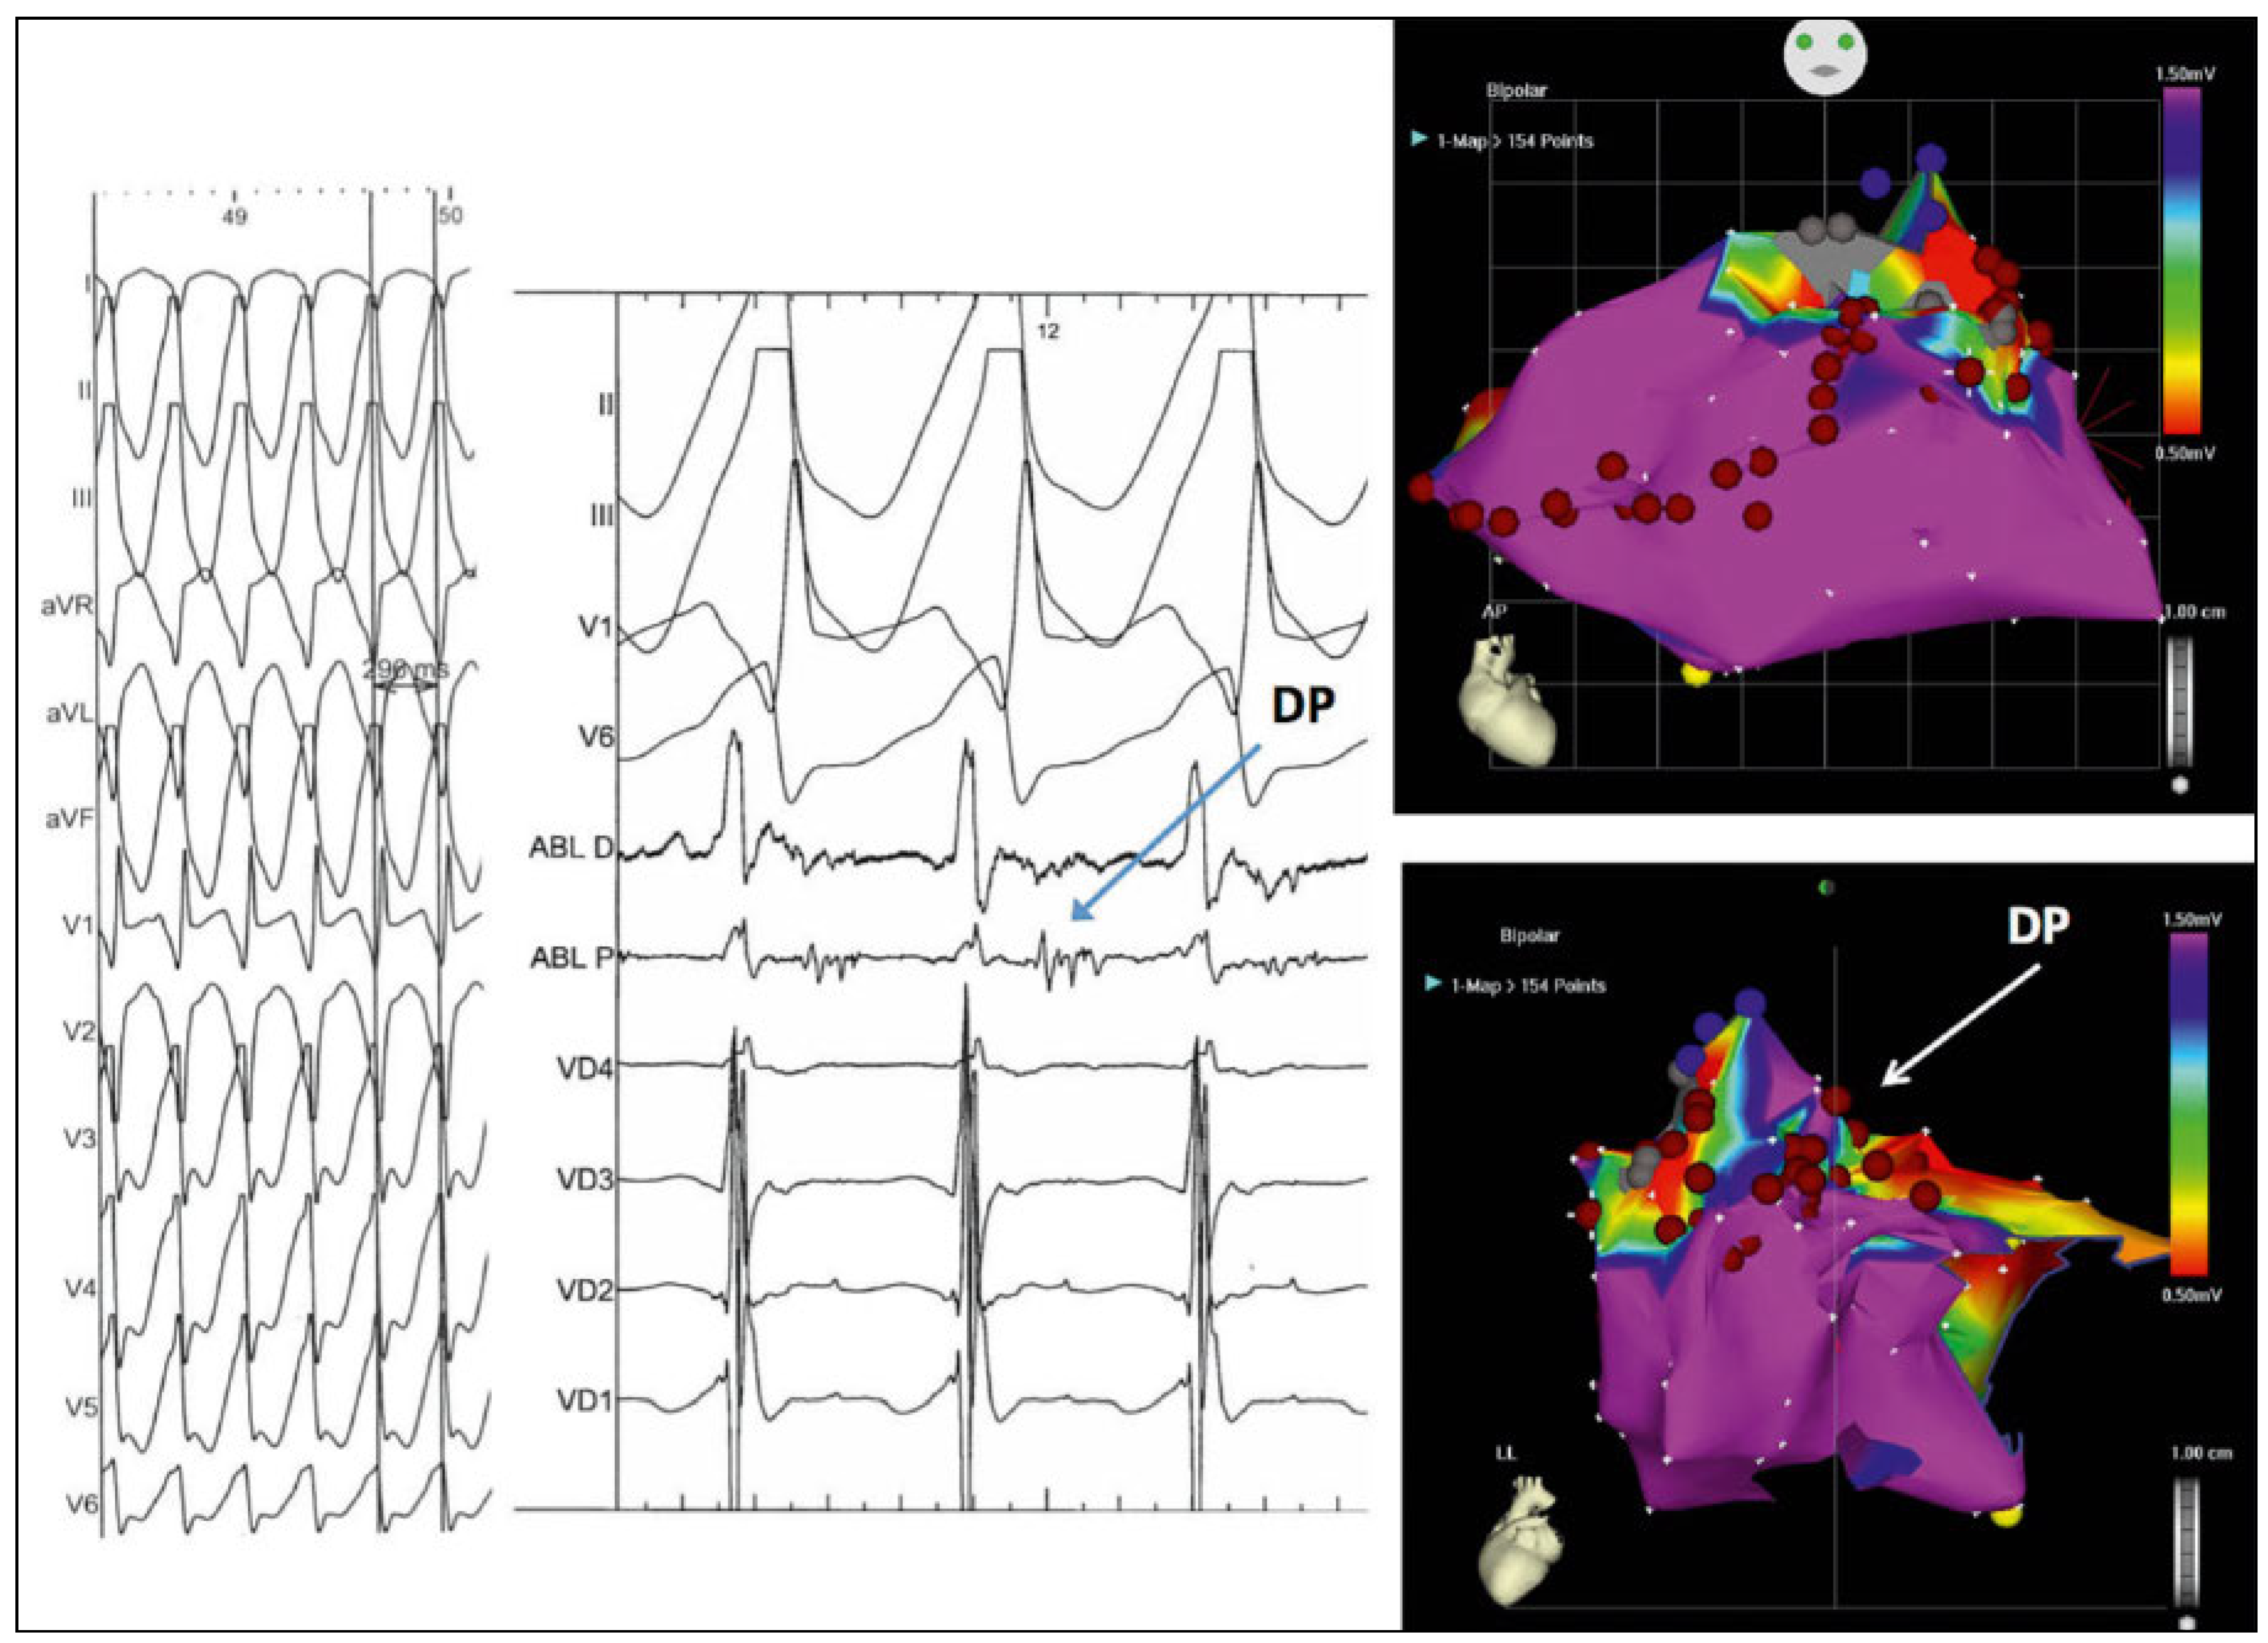

Figure 1. Left panel shows the clinical VT with a left bundle-branch block, left axis pattern and precordial transition in V5 compatible with a right ventricle free wall exit. Centre panel shows fluroscopic stills, anteroposterior (AP) view on top and left lateral below, with one catheter in the right pulmonary artery (PA) via the inferior vena cava, right atrium and right ventricle (RV) and a graduated pigtail catheter in the dextro-posed aorta and aortic root. White arrows indicate the calcified RV to PA conduit and the dashed white line indicates its junction with the RV. Right panel shows an electro-anatomical activation map of the RV, AP view on top and left lateral on the right. Orange hue indicates early activation and purple the latest activation, showing activation originating from the septal RV with later activation of the RV free wall and finally of the region close to the superior tricuspid annulus. Red dots indicate ablation lesions, delivered in a “linear” contiguous arrangement from the base of the conduit (grey zone indicating scar and the three blue dots) as well additionally at regions with fractionated and late potentials.

In our laboratory, an electroanatomic voltage map (Figure 2, right panel) and an activation map (Figure 1, right panel) of the right ventricle was created in sinus rhythm, confirming a low voltage zone with delayed activation in the septal outflow region, consistent with the VSD-left ventricular outflow patch, and another similar zone in the anterior outflow, consistent with the origin of the conduit to the pulmonary artery (Figure 1, middle panel: conduit indicated by white arrows on fluoroscopic views).